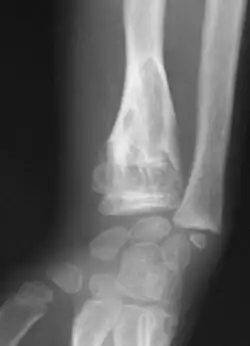

Enchondromas localized in the upper part of the humerus of the same patient